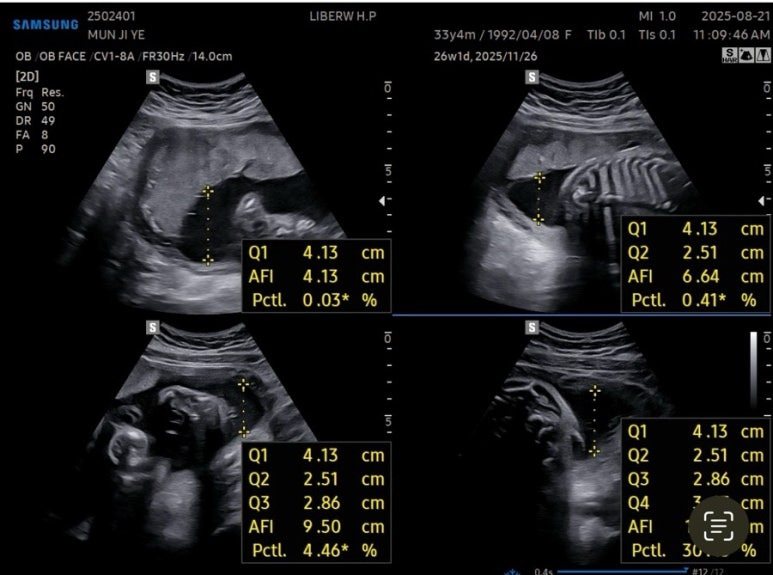

양수량도 적당했다